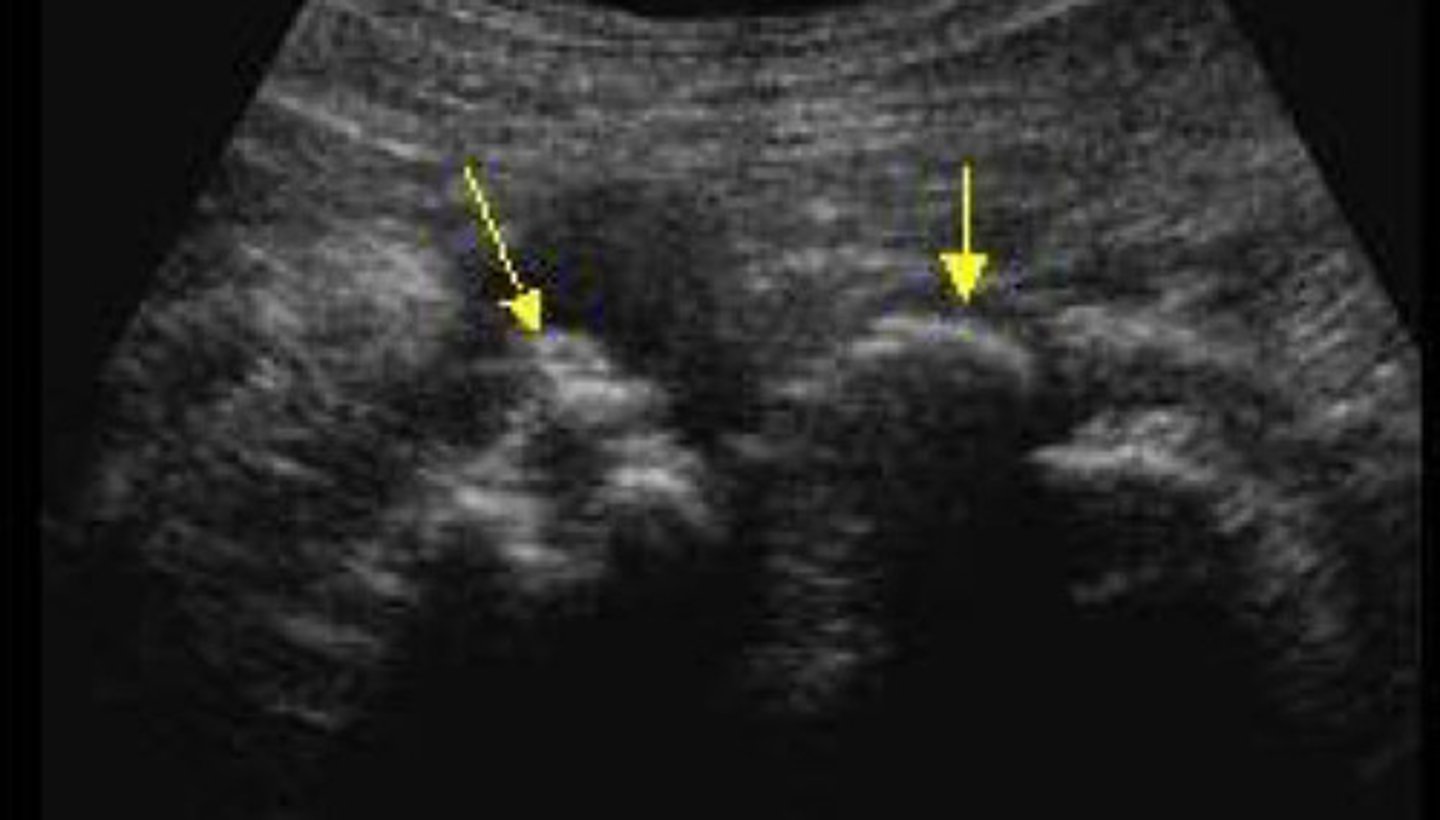

Echogenic focus or foci with posterior shadowing

Describe the sonographic appearance of nephrolithiasis

Nephrolithiasis

What does this image show

Stone difficult to identify in the sinus region

Stone now identified with the twinkle artifact